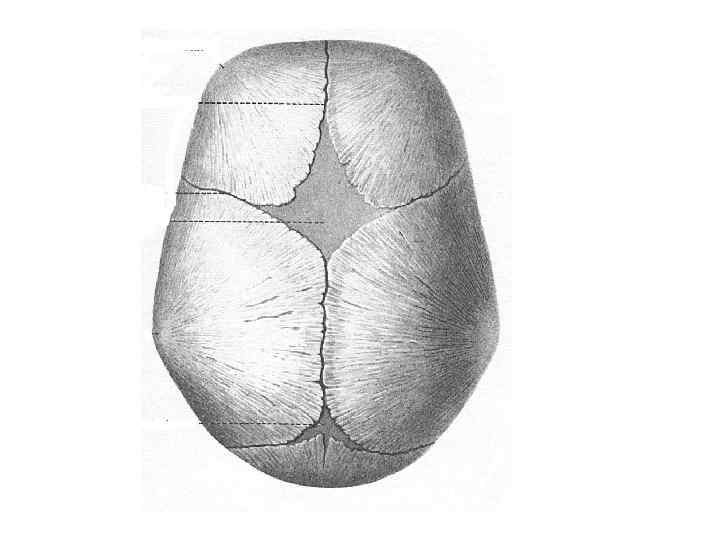

Череп (cranium)

Череп (cranium)

Череп (cranium)

Череп (cranium)

Череп (cranium)

Череп (cranium)

Череп (cranium)

Череп (cranium)

Череп (cranium)

Череп (cranium)

Череп (cranium)

Череп (cranium)